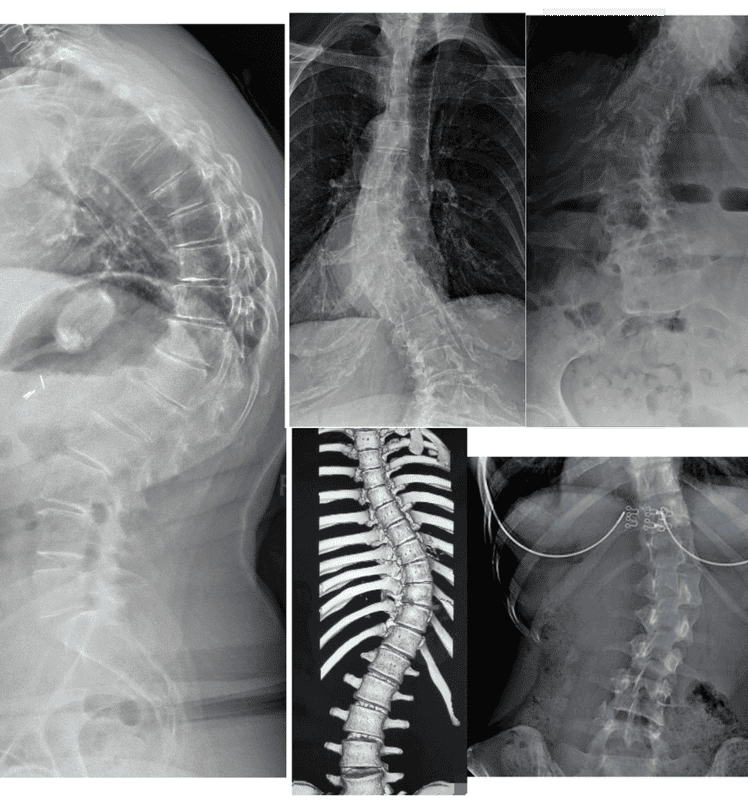

Measurable outcomes on X-ray. Here is what our co-managed patients have experienced.

Note: Individual results vary. All measurements taken on calibrated standing AP radiographs by the treating doctor. Cases shown with patient/guardian consent.

In-Brace Correction is normally 48% but we could see 63%.*

Out-of-Brace curves achieved 37.60% improvement if their curves are 20°-40°.

Results: curve correction: 76.9%, curve stabilization: 23.1%, curve progression 0%